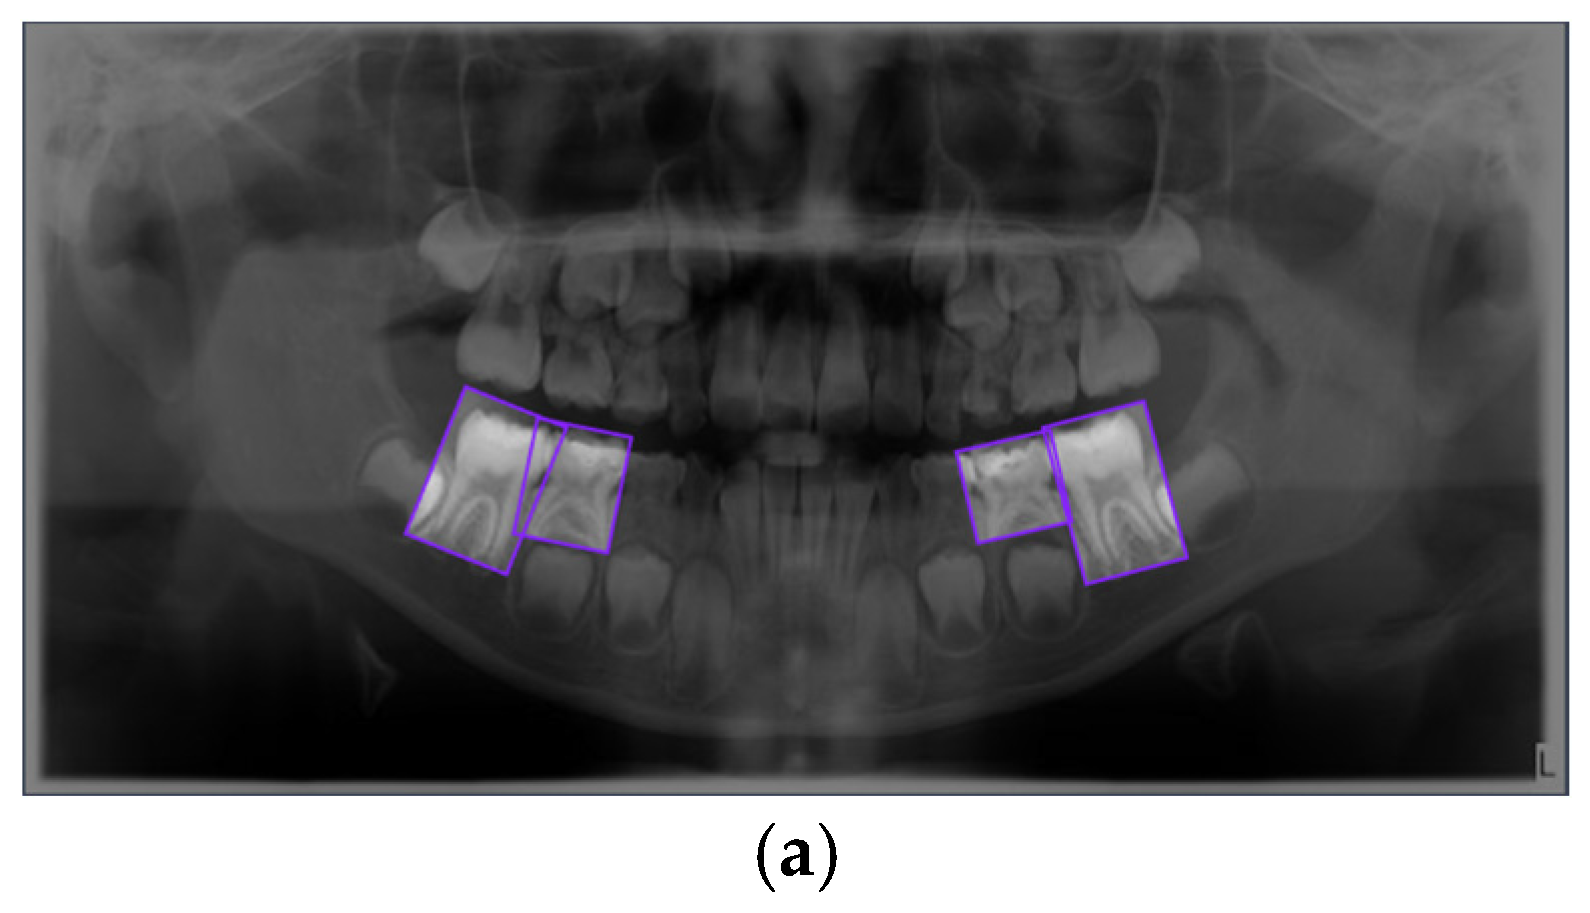

Figure 1. Representative examples of the four annotated dental conditions from the primary dataset. The images display examples of (a) Dental Caries, (b) Deciduous Tooth, (c) Root Canal Treatment, and (d) Pulpotomy. Bounding boxes indicate the ground-truth labels used for model training.

Figure 6. Examples of Successful Detection of YOLO Models for Different Dental Conditions. The images display representative examples of correct detections for (a) Dental Caries, (b) Deciduous Tooth, (c) Root Canal Treatment, and (d) Pulpotomy.